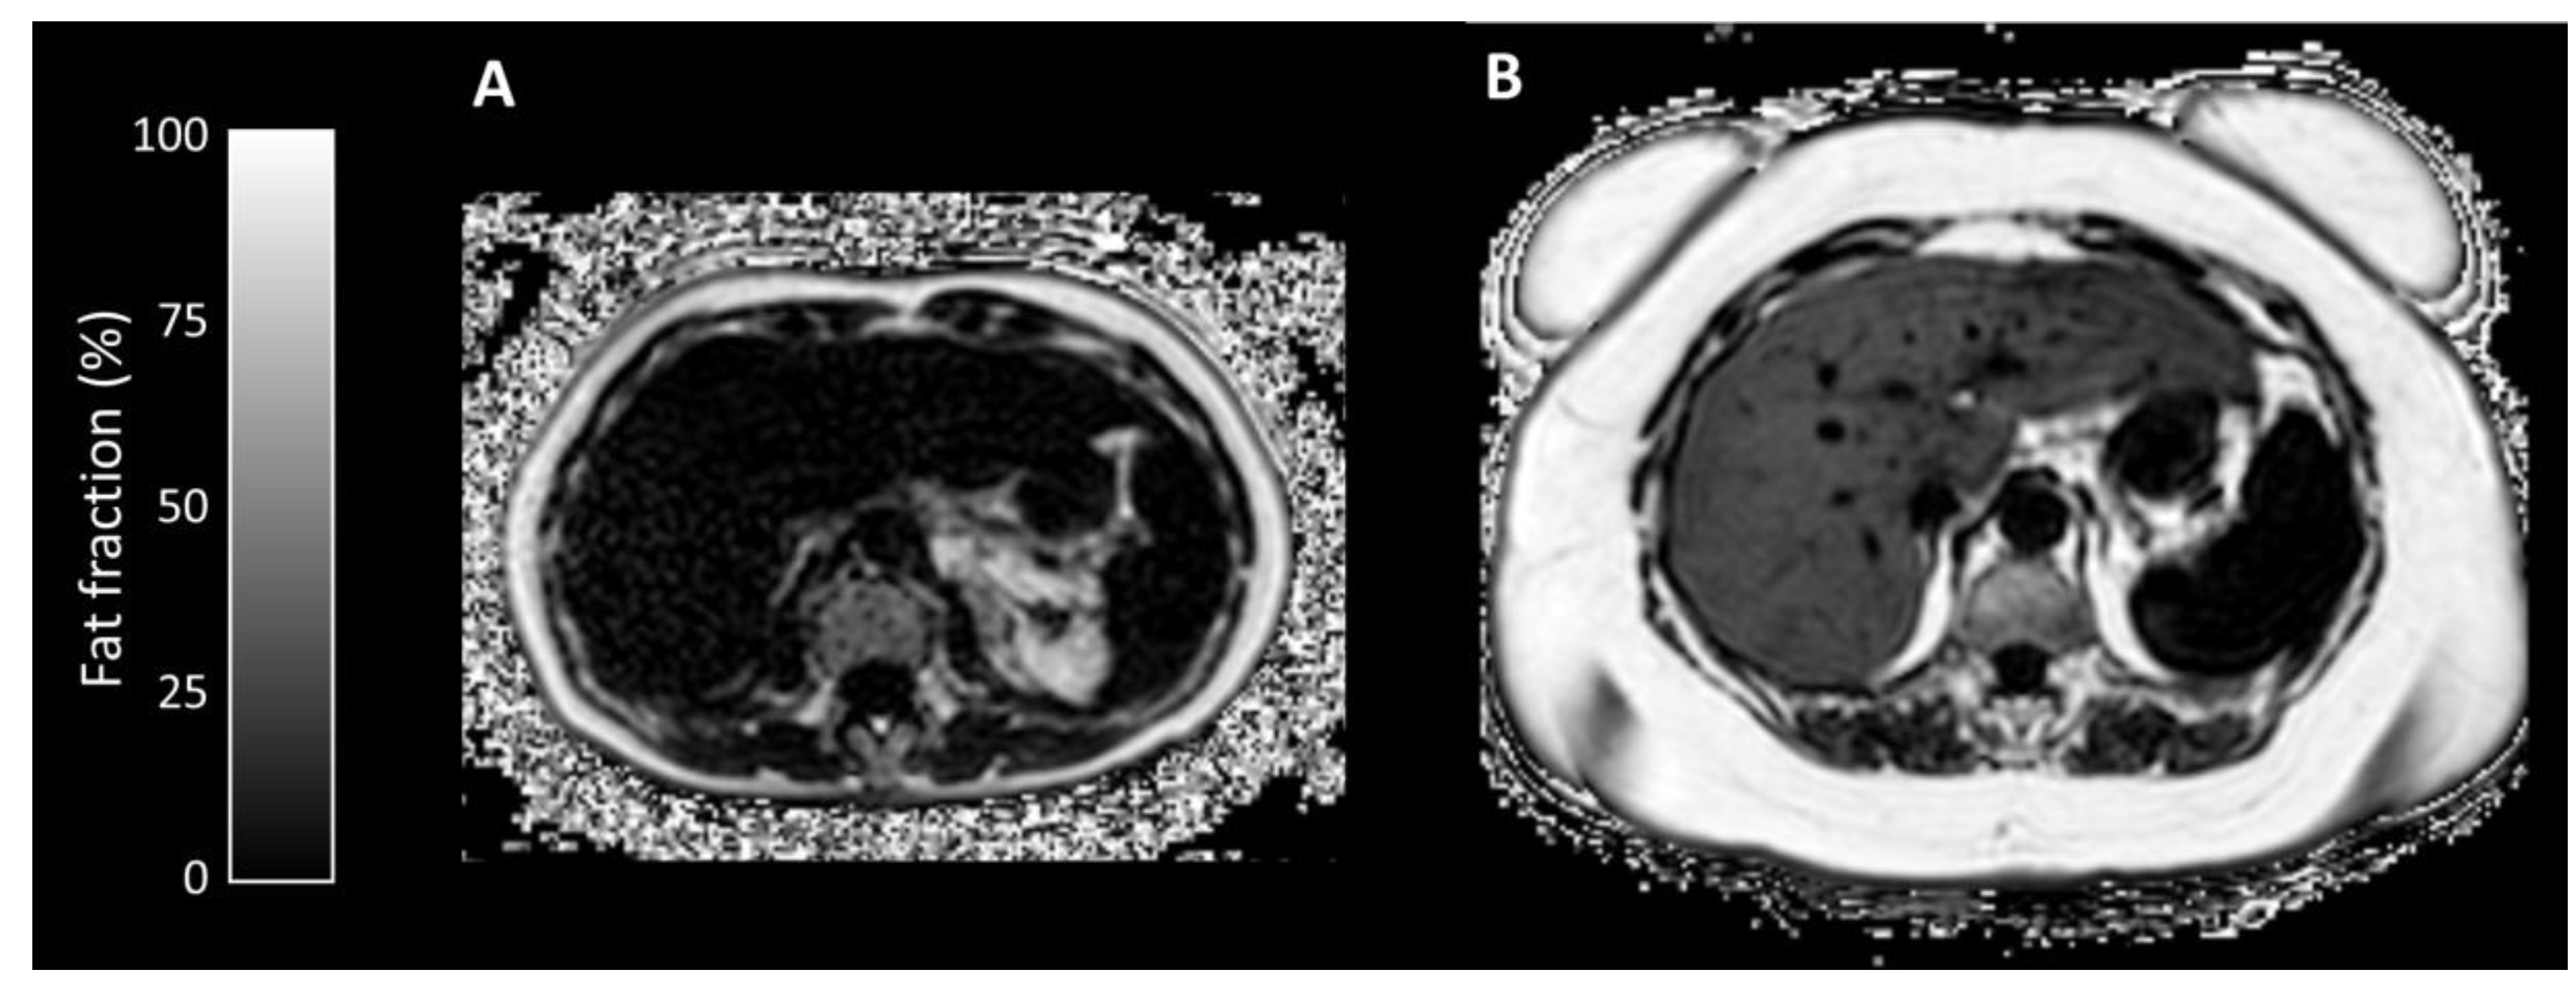

Appendix A.1.2. Proton Density Fat Fraction/T2* Mapping

Appendix A.1.3. T1 Mapping

Appendix A.2.1. Proton Density Fat Fraction/T2* Mapping

Appendix A.2.2. T1 Mapping

| Liver Fat Fraction (%) | 2.14 (1.4–4.2) | 10.90 (2.2–27.4) | 0.032 |

| Liver Iron Concentration (μmol/g) | 11.3 (10.4–38.9) | 16.0 (11.3–46.7) | 0.222 |

| Liver T1 (ms) | 715 (544–848) | 740 (594–919) | 0.873 |